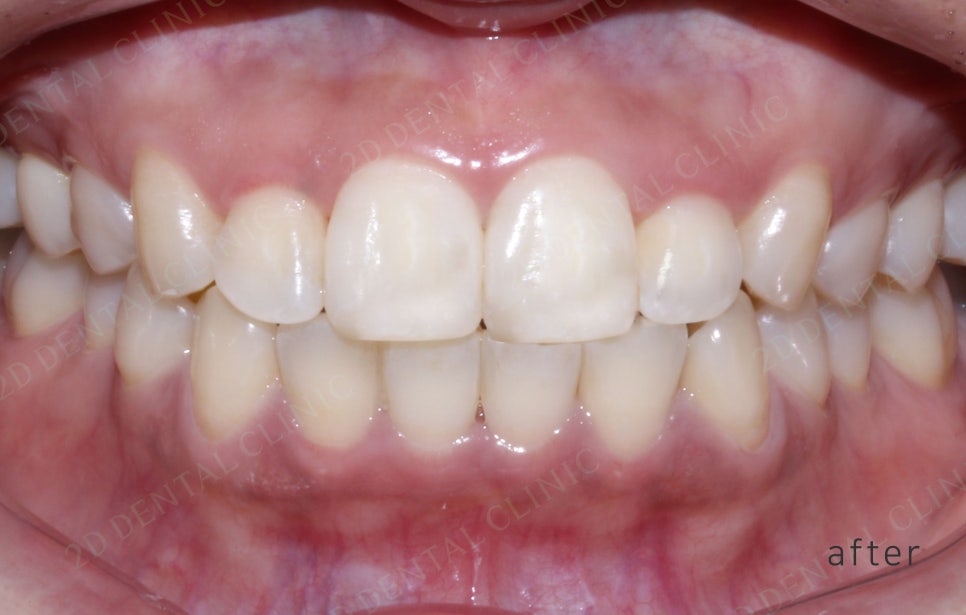

<교정 전/후 >

2D(투디)교정 앞니덧니,반대교합 치아교정

191일(약 6개월)후 투디교정 완료.

전,후 사진만 봐도 치아 배열이 잘

정돈된게 보이시나요!?

치아 배열이 가지런해 지다보니

확실히 입술도 편안해 보이는게 느껴져요♪♪